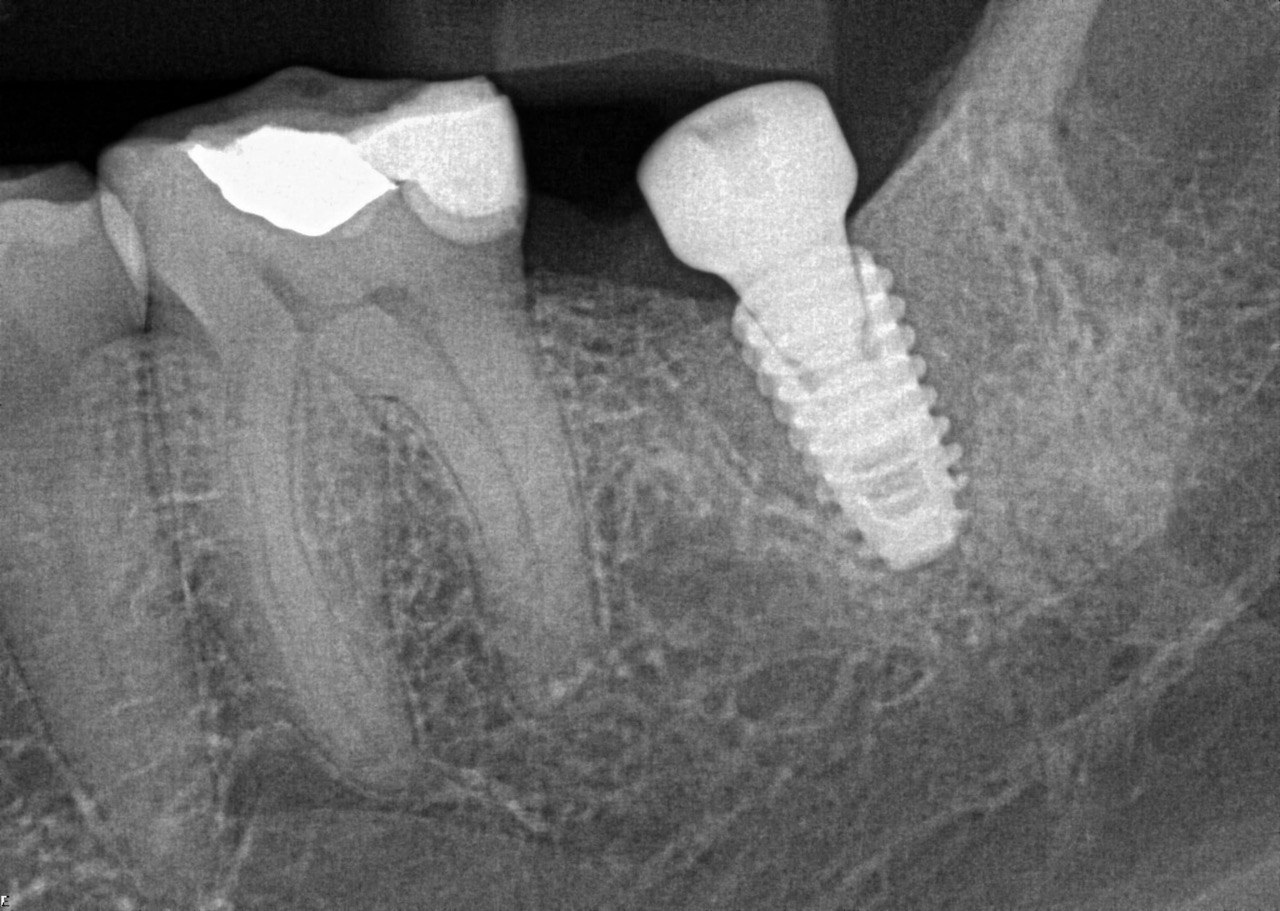

12. What option can be selected regarding the implants seen in this X ray?